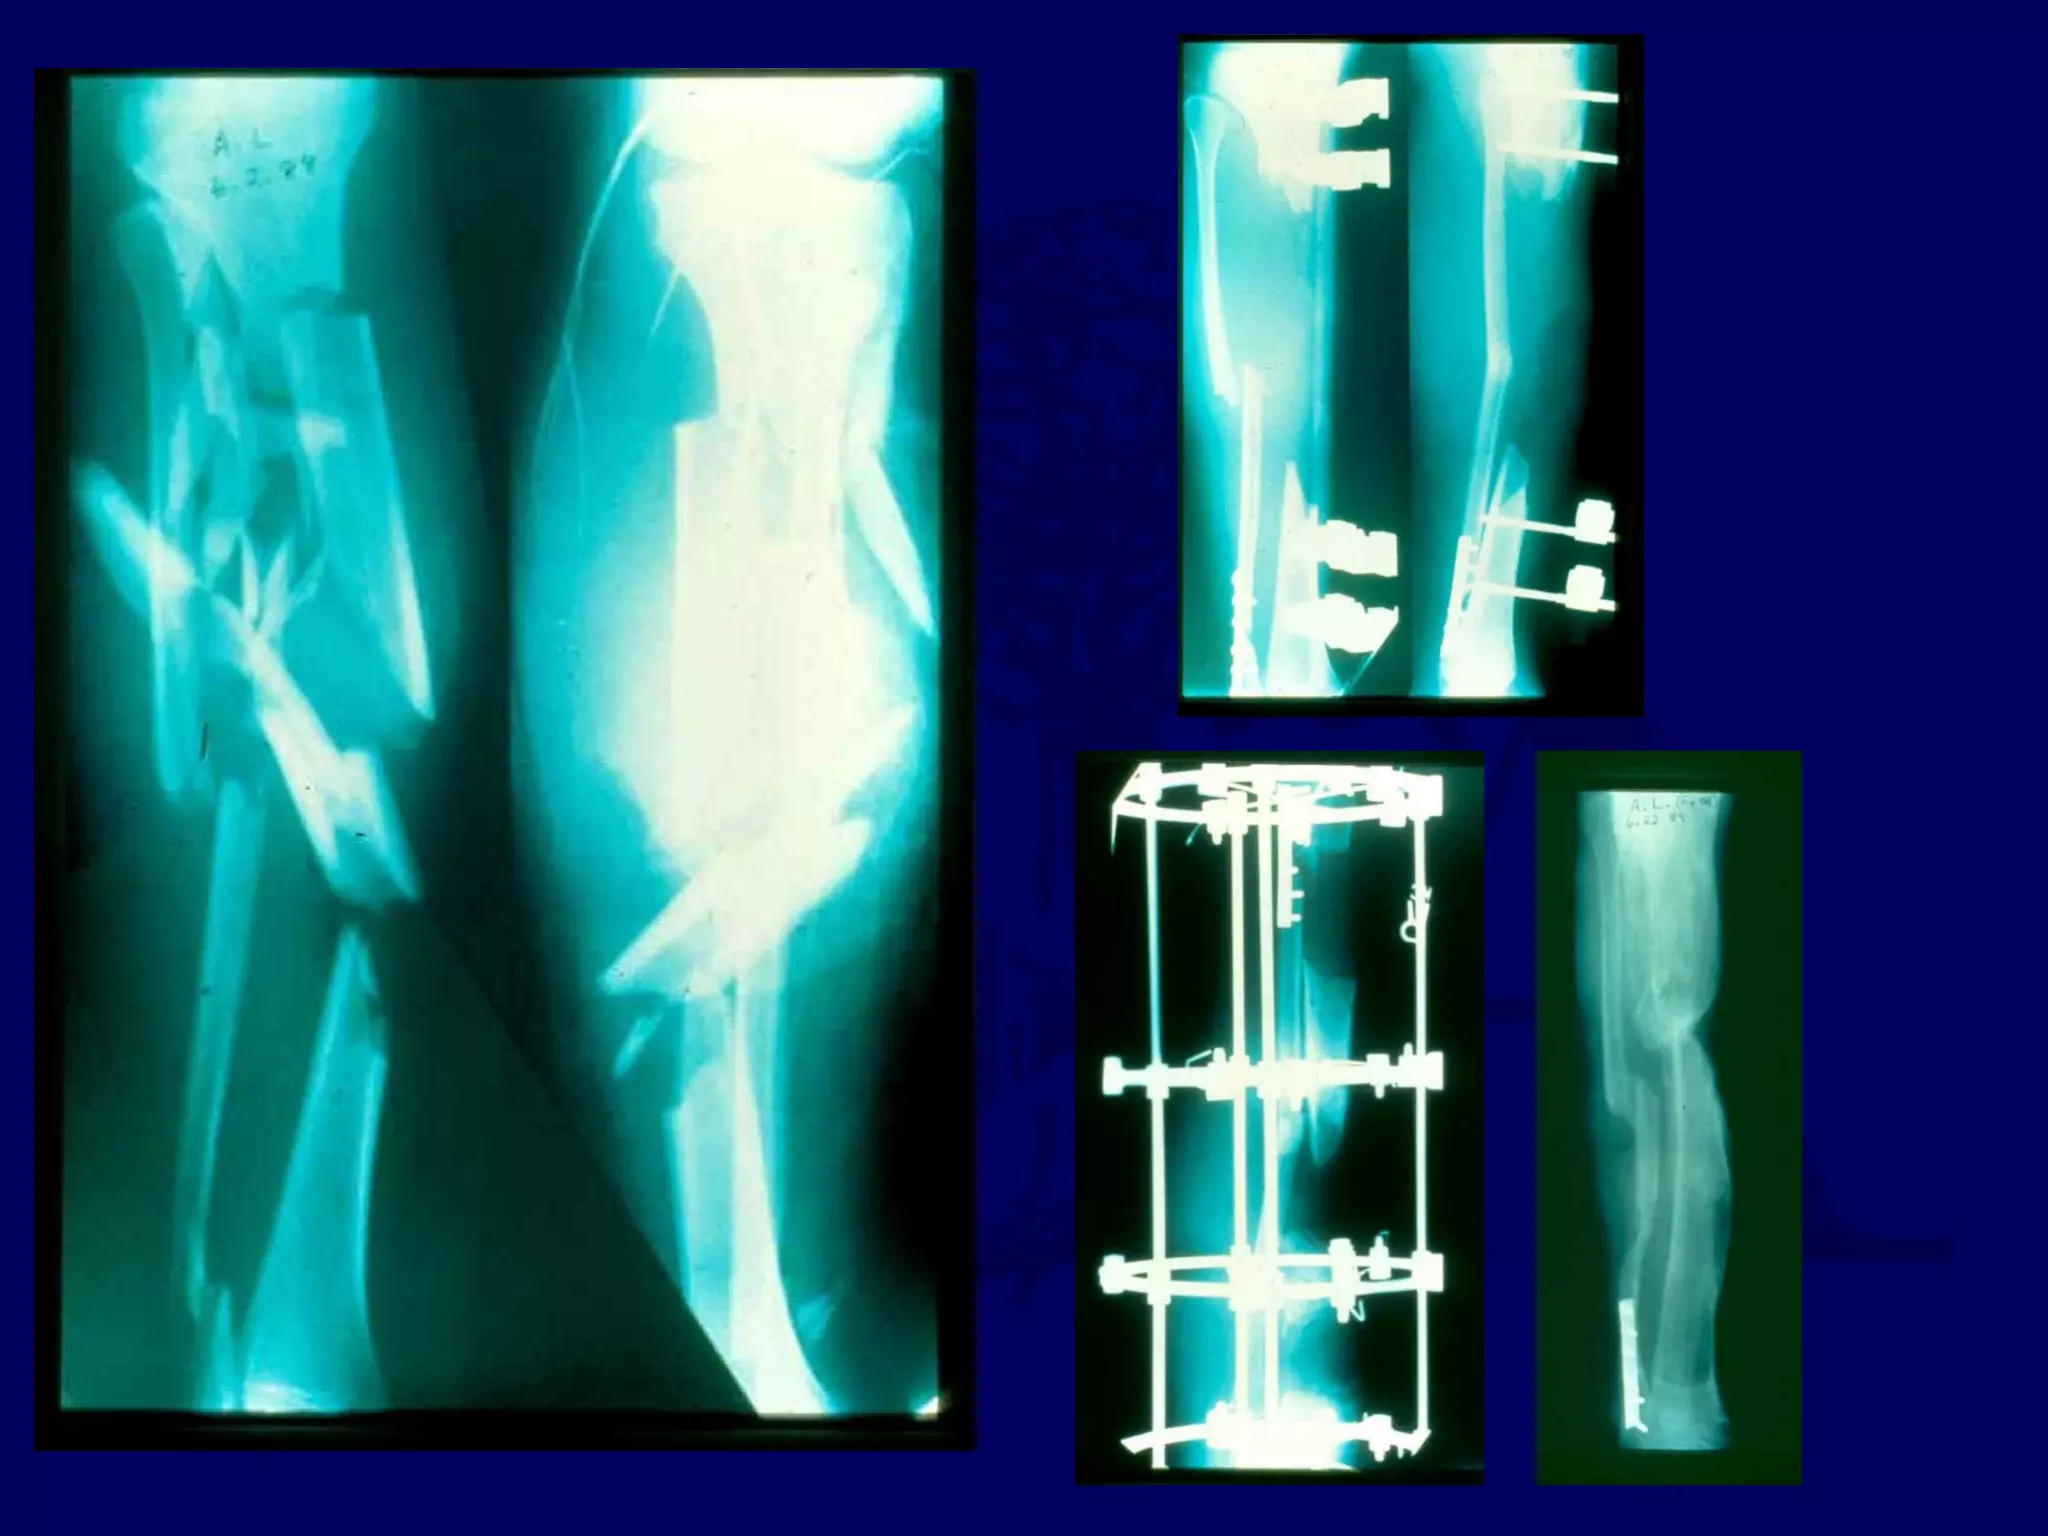

Techniques in Amputations

Skin Traction

Dates Back Over 100 years

Used Over Open Wounds to Save Length

Elastomeric Sleeves Can be Used Instead of Glued Stockinette

Home Set-up Possible

Start at 2 lbs, Slowly Work Up Towards 5 lbs

Decrease Weight if Skin Blisters

Traction facilitated closure and preservation of length.

Revision performed after 18 months because of scar irritation.